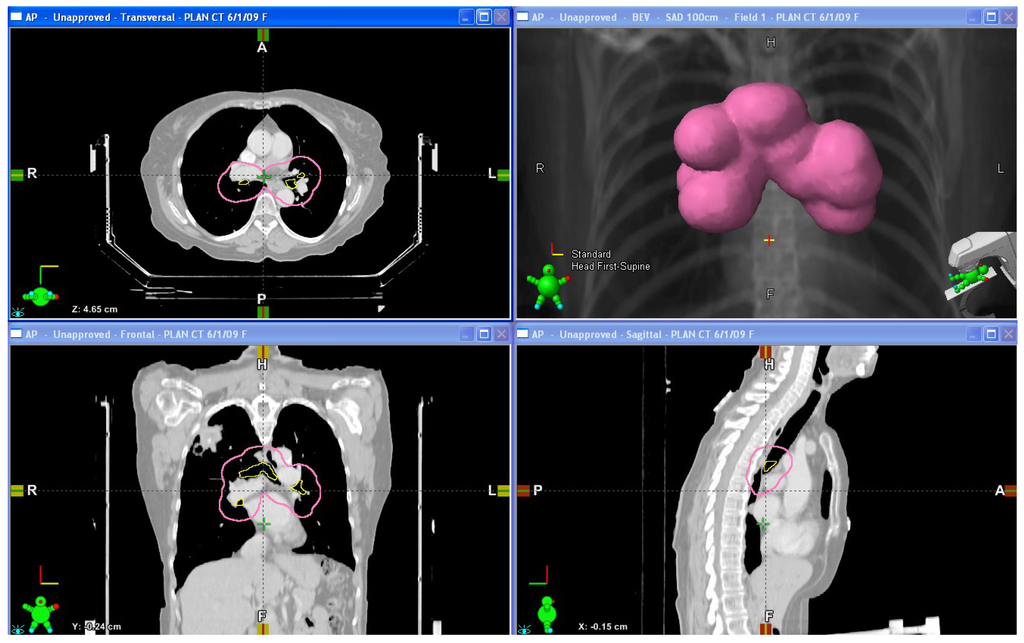

Figure 1. Diagrams of the proximal bronchial tree and the surrounding 2 cm avoidance zone. Upper left: Axial view; Lower left: Coronal view; Upper right: 3-dimensional representation of the avoidance zone; Lower right: Sagittal view.